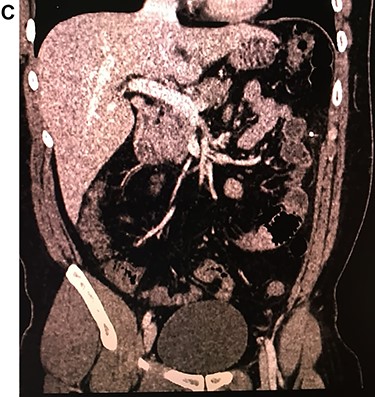

Leukocytosis with neutrophilia was detected, along with an elevated C-reactive protein. On the CT, a high-density object was seen in the descending colon; the object resembled a 4.5 cm needle that perforated the whole extent of the colonic wall. Surrounding this area there was inflammation with mesenteric edema. No lymph nodes or other masses were detected (Fig. 1A, 1B, 1C).

With these findings, surgical consultation was required, and surgery was decided on a laparoscopic approach.